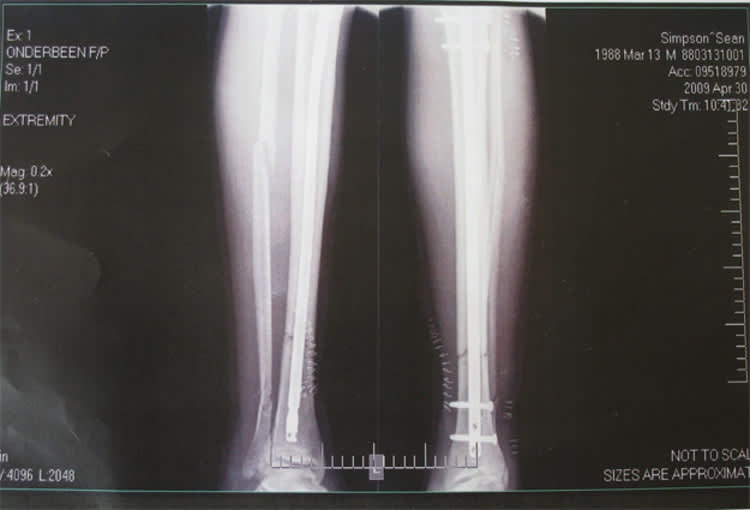

Simpsonxray

"Ich schaute zu meinem Fuss und sah das ganze Blut. Ich war geschockt. Zum Glück eilten mein Vater und Bruder herbei. Die beiden blieben echt cool. Mein Bruder hielt meinen Fuss, während mein Vater den Stiefel aufschnitt. Bis der Krankenwagen kam, dauerte es eine halbe Stunde, und meine Schmerzen wurden immer schlimmer. Es waren schreckliche Minuten", schilderte Simpson.